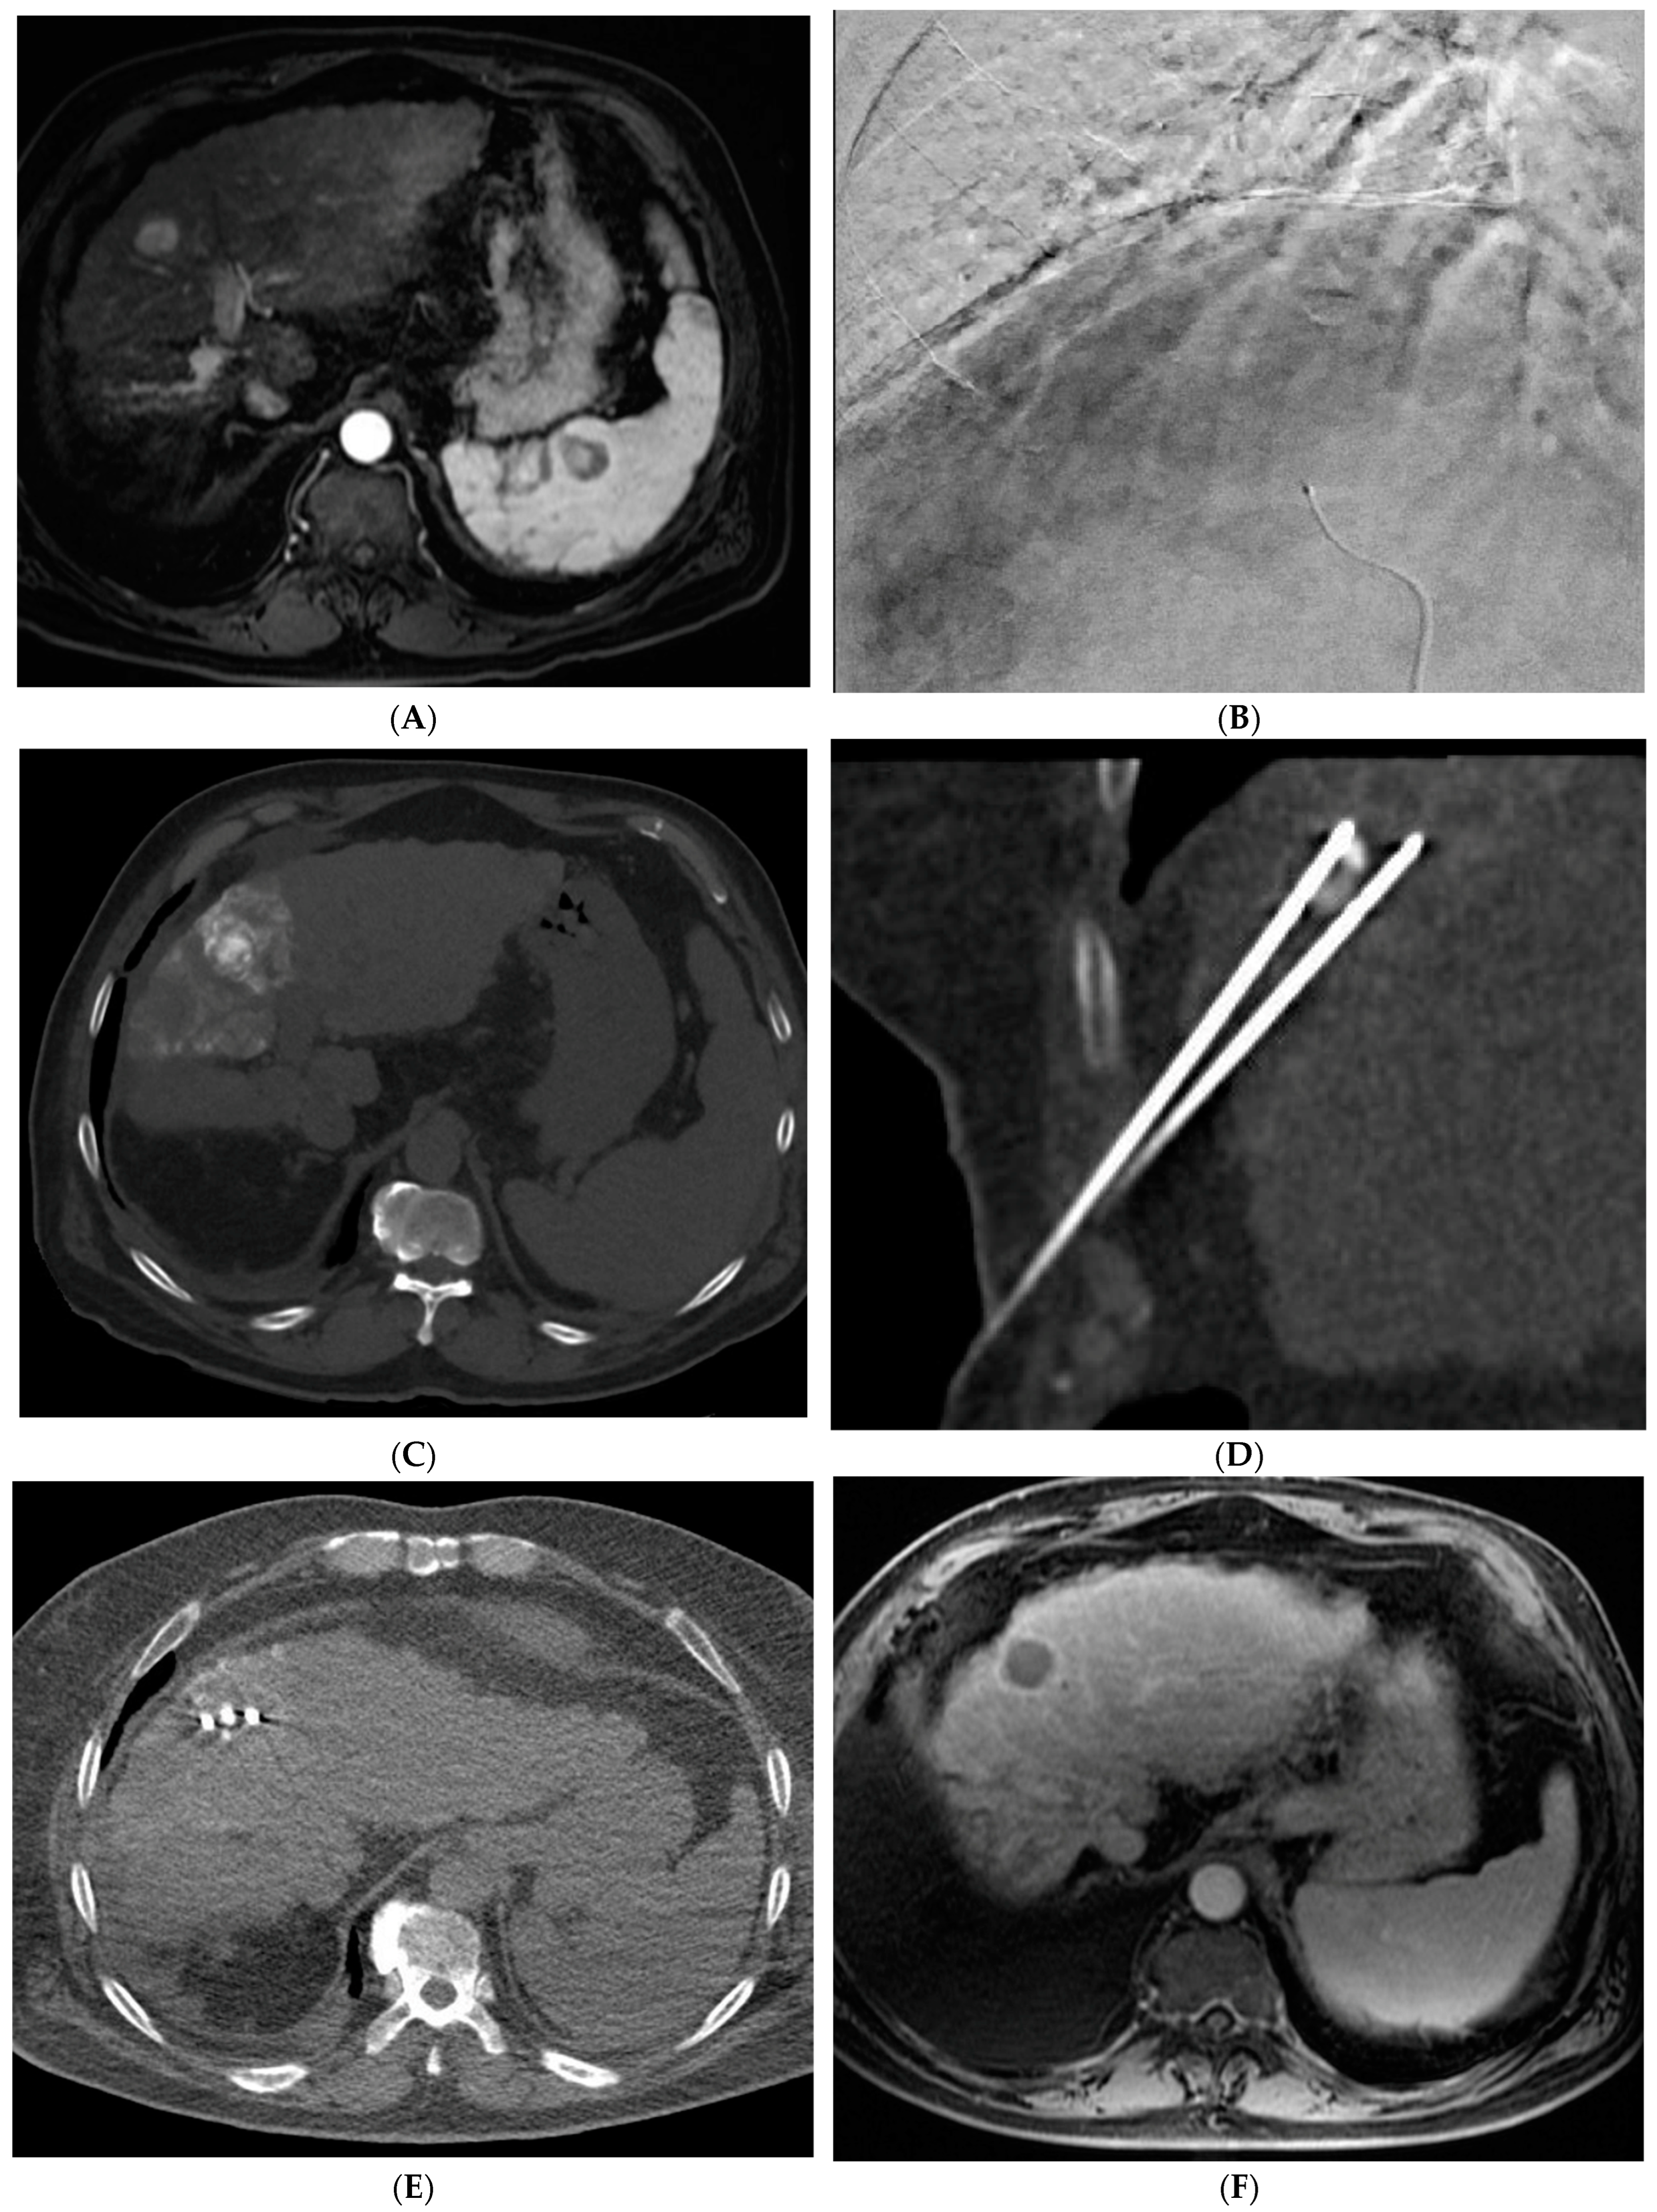

Variations in TARE include radiation segmentectomy and lobectomy [10]. In patients in which resection or ablation is not feasible, radiation segmentectomy can offer an ablative level treatment dose to lesions confined to less than two segments while sparing the remaining normal liver parenchyma [10] (Figure 3). The RASER trial demonstrated that radiation segmentectomy in patients with a solitary HCC tumor in an unfavorable location for ablation resulted in high rates of complete response (24/29 patients, 83%) with low rates of adverse events [38]. In the DOSISPHERE-01 study, patients with unresectable HCC were randomized to either standard dosimetry (120 ± 20 Gy) to the diseased lobe or personalized dosimetry (>205 Gy) to the index lesion. Patients in the personalized dosimetry group had significantly higher rates of objective response to therapy with similar rates of adverse effects [39]. Radiation lobectomy is yet another application of 90Y that involves administering a higher dose to the diseased lobe of the liver, with the goal of inducing tumor death and atrophy of the diseased lobe with resultant compensatory hypertrophy of the normal lobe. This concept can allow patients who would not otherwise be candidates for surgical resection due to a small future liver remnant (FLR) to be able to undergo resection [10].

Figure 3.

73-year-old man with non-cirrhotic HCC treated with 90Y radiation segmentectomy. (A) Arterial phase MRI showing a 4 cm arterially enhancing lesion in hepatic segment 5. (B) Delayed phase MRI showing washout of the lesion. (C) Intraprocedural CTA demonstrating supply to the posterior aspect of the mass from one of the segment 5 branch arteries. (D) Intraprocedural CTA demonstrating supply to the anterior aspect of the mass from a separate segment 5 branch artery. The Y90 dose was delivered as a split dose between these two arteries. (E) Follow up arterial phase MRI 3 months after treatment demonstrates wedge-shaped post-treatment changes in hepatic segment 5 with expected parenchymal enhancement and capsular retraction with no residual enhancement of the targeted tumor. (F) Follow up delayed phase MRI demonstrates no wash-out of the enhancing parenchyma to suggest residual viable tumor, consistent with complete response.

The combination of locoregional therapies is also an area of interest. In a meta-analysis, the combination of TACE and RFA compared to surgical resection showed no difference in overall survival but reduced complications in the combination therapy group [65]. The ethiodized oil retention within HCC following cTACE can also be used as a marker to guide percutaneous ablation (Figure 4). Stereotactic body radiotherapy (SBRT) is currently being studied in combination with TACE with promising results. In a propensity-scored matched analysis by Wong et al., patients who received the combination of SBRT + TACE had significantly higher one- and three-year overall survival and improved radiological disease control [66]. There is also interest in using SBRT in cases of local relapse following TACE. A phase III trial was closed early due to slow accrual, but results showed superior local control of SBRT versus repeat TAE/TACE [67]. SBRT remains a promising non-invasive treatment for unresectable HCC. Further research is needed to define its role within the HCC treatment paradigm.

Figure 4.

72-year-old man with HCV cirrhosis and HCC treated with combined cTACE and cryoablation as a bridge to transplant. (A) Arterial phase MRI demonstrates a 2.2 cm segment 4a hypervascular lesion. (B) Digital subtraction angiography images during cTACE procedure demonstrate that the tumor was supplied by both the segment 4a branch vessel (image shown) and segment 2 artery (not shown). cTACE was performed using doxorubicin 50 mg, cisplatin 100 mg, and mitomycin 10 mg followed by PVA 150–250 micron particles. (C) A non-contrast CT scan performed on post-operative day 1 demonstrates a heterogeneous uptake of ethiodized oil within the tumor. Cryoablation was then performed using two probes. Coronal and axial CT images from the procedure demonstrate the probes adjacent to the ethiodized oil staining (D) and the ice ball (E). (F) A follow up contrast enhanced MRI in the arterial phase demonstrates no residual viable tumor.